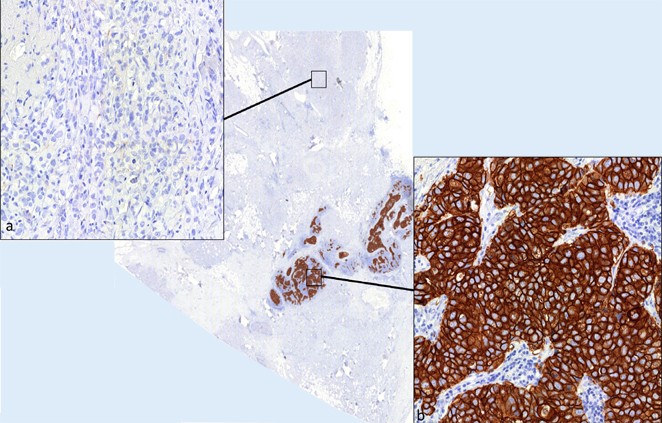

Ein Beispiel eines artifiziell HER2-positiv „gemachten“ Mammatumors ist in Abb. 2 a, b dargestellt. Dieses Gewebe wurde zu Demonstrationszwecken alkoholfixiert. Bei negativem FISH-Befund (Abb. 2 c) besteht teilweise eine deutliche immunhistochemische HER2-Positivität (3+).

Abb. 2

figure 2

Artifizielle HER2-Positivität in der IHC nach Alkoholfixation (ab). Der FISH-Befund bleibt klar negativ (c)